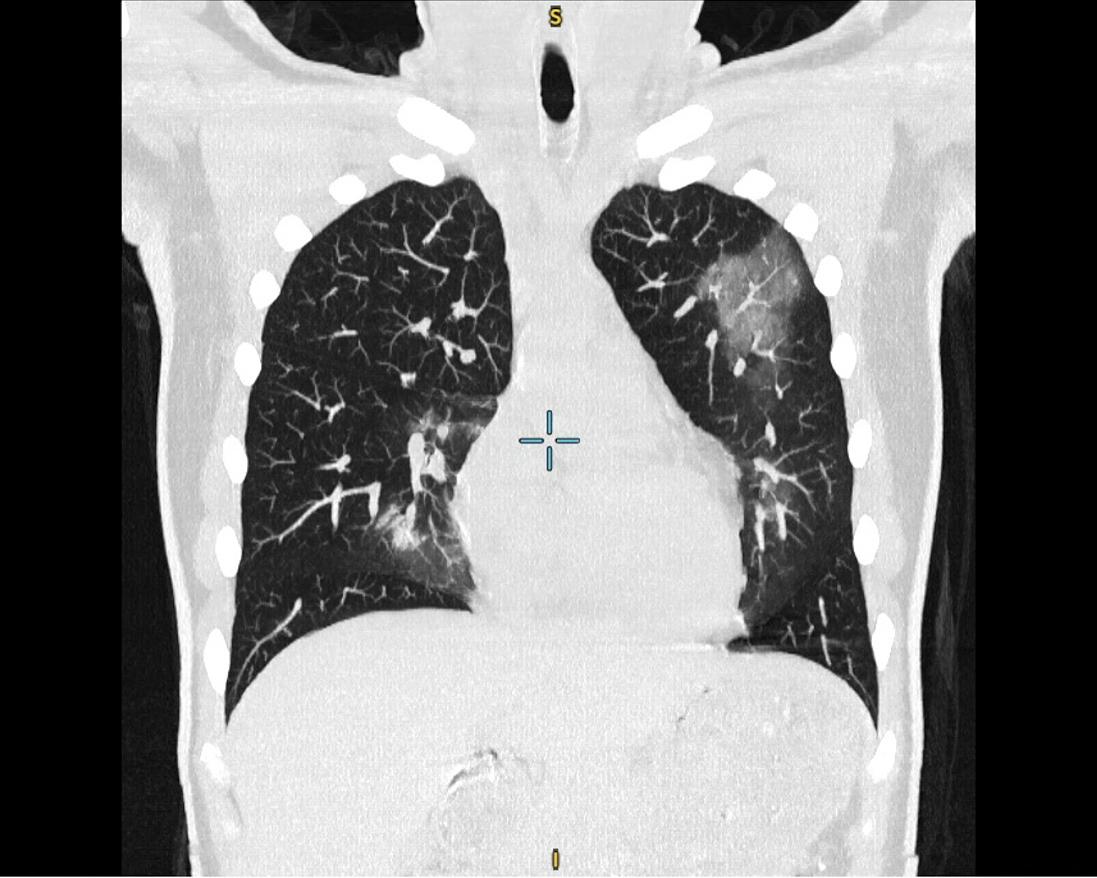

Chị N.T.T (35 tuổi) đến Hệ thống Y tế Thu Cúc TCI khám với biểu hiện ho khan, người mệt mỏi, tức vùng mũi sau 1 tháng mắc Covid-19. Bác sĩ Nội khoa tại TCI đã thăm khám và chỉ định chị T. chụp X-quang ngực thẳng. Kết quả trên phim chụp X-quang phát hiện có bất thường: Hình ảnh đám mờ không đồng nhất ngang mức cung trước xương sườn II-III bên trái. Kết hợp với ảnh chụp CT, chị T. được chẩn đoán viêm phổi đông đặc và xơ hóa phổi hậu Covid-19.

Hình ảnh phổi của bệnh nhân N.T.T bị tổn thương sau khi nhiễm SARS-CoV-2

Được biết, chị N.T.T chỉ là một trong rất nhiều người bệnh đến Thu Cúc TCI thăm khám hậu Covid và phát hiện tổn thương tại phổi. Theo Tiến sĩ, Bác sĩ CKI Nguyễn Đức Hoan - Giám đốc Phòng khám ĐK Thu Cúc 32 Đại Từ (Nguyên Phó Viện trưởng kiêm Chủ nhiệm Khoa Nội tổng hợp tại Viện điều trị cán bộ cao cấp Quân Đội – BV TƯQĐ 108): "SARS-CoV-2 có ái lực mạnh mẽ với cơ quan hô hấp, gây tổn thương và để lại nhiều di chứng tại phổi. Các vấn đề về phổi thường gặp hậu Covid-19 gồm: viêm phổi, xẹp phổi, tràn dịch màng phổi, tràn khí màng phổi, áp xe phổi, đông đặc phổi, xơ phổi, tắc nghẽn mạch phổi,… Tổn thương phổi có thể xuất hiện ở cả trường hợp có bệnh lý nền hoặc không. Nếu không được điều trị kịp thời, các di chứng này sẽ gây suy giảm nghiêm trọng chức năng hô hấp và có thể đe dọa đến tính mạng người bệnh."